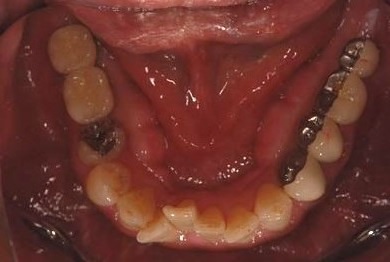

インプラントの症例写真 IMPLANT

インプラント治療

| 性別/年齢 | 男性 / 59歳 | ||||||||||||||||||||||||||||||||

| 治療方針 | 欠損部分インプラント治療により、機能的・審美的回復を行う。 | ||||||||||||||||||||||||||||||||

| 治療内容 | インプラント2本、ハイブリッドセラミック2本 | ||||||||||||||||||||||||||||||||